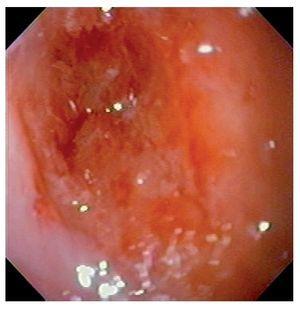

El procedimiento fue efectuado bajo sedación consciente, utilizando un equipo ultrafino (Olympus N180) de calibre de 5.2 mm, permitiendo la identificación de una pequeña adherencia en el paladar blando e hipofaringe, así como la presencia de un puente fibrótico proximal al ápice del receso piriforme derecho, mismo que se rompió al atravesar el endoscopio. En el esófago proximal, 3 cm debajo del cricofaríngeo, fue identificada un área de estenosis concéntrica, puntiforme y no franqueable al paso del endoscopio (Figura 4).

¿ Figura 4. Aspecto endoscópico de la estenosis esofágica.